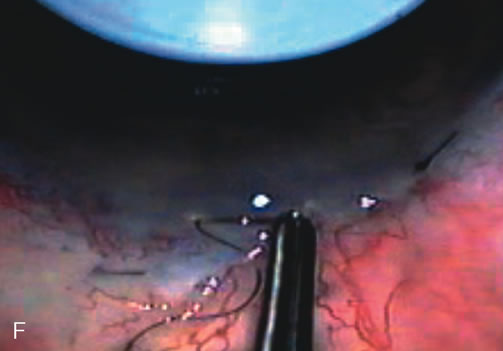

Fig. 4. Viscocanalostomy with deep sclerectomy and phacoemulsification. Nonpenetrating filtration procedures (NPFS) may be combined with phacoemulsification. Patients with mild disc damage and a history of limited topical drug therapy are the best candidates. Patients who require an IOP in the low teens are not good candidates for NPFS. By definition, NPFS is designed to lower IOP without penetrating into the anterior chamber, thereby avoiding the complications associated with trabeculectomy. Viscocanalostomy is intended to allow aqueous to percolate through a trabeculodescemetic membrane into a subscleral cavern created by the deep sclerectomy. The aqueous diffuses from the cavern into the dilated ostia of Schlemm's canal and into the episcleral venous plexus. A. Fashion a uniform 300-micron superficial scleral flap 1 mm into clear cornea. B. Construct a second 600-micron deep flap that facilitates the unroofing of Schlemm's canal, seen as the darker area. C. Use viscoelastic to dilate the ostia of Schlemm's canal. The major problem with viscocanalostomy is the eventual closure of the ostium decreasing flow to the episcleral plexus. D. Dissect the deep flap anteriorly into clear cornea creating the trabeculodescemetic membrane. This membrane is clearly seen between the scleral spur and the bend of the deep flap. The integrity of this membrane ensures the nonpenetrating portion of the surgery. Another problem with NPFS is the eventual fibrosis of this initially transparent membrane requiring goniopuncture. E. Deep sclerectomy gets its name from removal of the deep flap. Removal of this flap creates the potential subscleral space for accumulation of aqueous before it enters Schlemm's canal and exits the episcleral venous plexus. After removal of the deep flap, the superficial flap is sutured into place and conjunctiva closed. Approximately half of these procedures develop a shallow bleb.